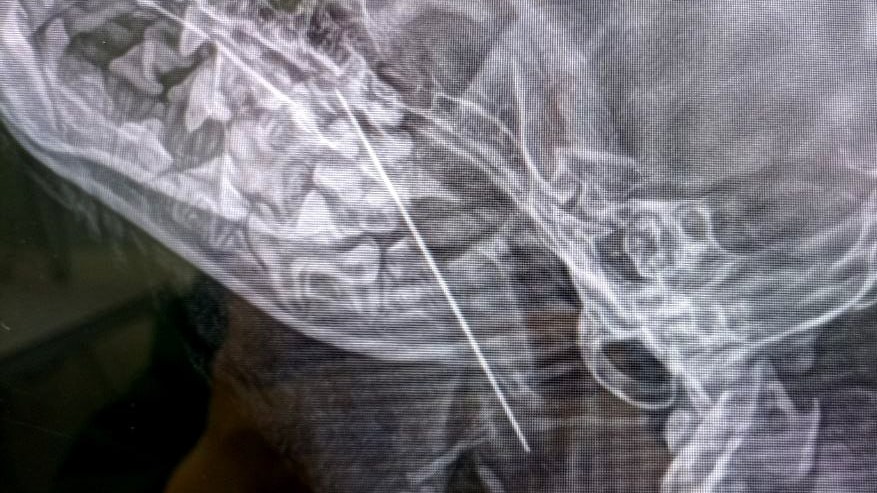

Фото: пресс-служба Мосветобъединения

Столичные ветеринары Тушинской клиники извлекли большую швейную иглу из 10-месячного щенка йоркширского терьера по кличке Маруся. Об этом во вторник, 28 января, сообщили в пресс-службе «Мосветобъединения».

Собаку привезли в клинику с жалобами на кашель. Незадолго до этого Маруся стащила с хозяйской кухни кусок форели и съела его. Сначала хозяева предположили, что она подавилась рыбной костью. Однако врачи сделали щенку рентген и выяснили, что в мягких тканях его глотки застряла игла. Пушистую пациентку отправили на экстренную операцию, в ходе которой хирург Наталья Польдяева успешно извлекала инородный предмет.

— Через 30 минут Маруся пришла в себя после наркоза и уехала домой полностью здоровым щенком, — передает официальный Telegram-канал организации.

Крупную швейную иглу достали из щенка йоркширского терьера в Москве Фото: пресс-служба Мосветобъединения